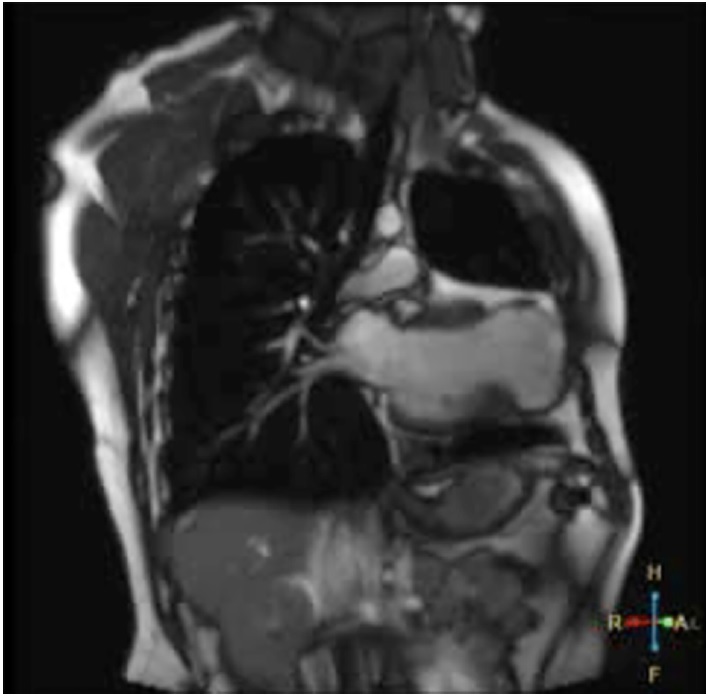

Within 24 hours from discharge, the patient had fever, poor general condition, raspberry tongue, bilateral palpebral edema, and conjunctivitis. The patient was hospitalized. Laboratory tests showed inflammation and positive SARS-CoV 2 IgG, and a repeat echo-Doppler (Figure 1) showed aneurysmal dilation in both coronary arteries with preserved ventricular function (Table 1 outlines coronary values with their corresponding Z scores upon successive echocardiography monitoring). The condition was reassessed as MIS-C. The patient received immune-mediated treatment and platelet aggregation inhibitors with gamma globulin (2 g/kg/dose), methylprednisolone (10 mg/kg/dose, 3 pulses), ASA 5 mg/kg/day. The patient showed mild clinical and analytical improvement. Heart monitoring after 5 days revealed similar characteristics. The patient was classified as treatment-resistant, and infliximab was prescribed (5 mg/kg). He showed good progression, with significant clinical and cardiovascular improvement, and was discharged after 16 days. Cardiologic and rheumatologic workup plus platelet aggregation inhibitor and anti-inflammatory therapy were scheduled.

2D Doppler Ecography

Fig. 1 2D echo-Doppler (vessel short axis): Right coronary artery (above) and left coronary artery (below) are shown.